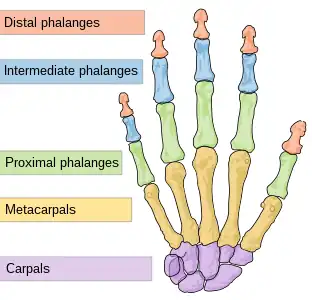

Hand bones. Note the thumb has no blue middle phalanx.

Hand bones. Note the thumb has no blue middle phalanx. Hand Joints, X-ray

Location

Finger fractures are identified by the bone on which they occur. Fingers are numbered 1 to 5, with 1 being the thumb. The distal (tip) finger bones are divided into tuft (the very tip of the bone, at the end of each finger), shaft (the thinner middle section), and base. The rest of the finger bones (the middle finger bones, and the proximal or innermost finger bones) are divided into base, shaft, and condyle (outer end). Extensive tendons surround the joints and move the fingers. On the front and back of each finger is a digital nerve and artery; these can also be injured when the finger is broken.[1]

The AO Foundation/Orthopaedic Trauma Association (AO/OTA) classification generates language-neutral numeric codes for describing broken fingers. They run 78[meaning a fracture of the phalanges of the hand].[number-code of the finger, with thumb=1 and the little finger=5].[number-code of phalanx, counting 1 to 3 outwards from the hand].[number-code of location on the bone, with 1 being the inner end, 3 the outer, and 2 in-between]. So, for instance, 78.1.1.1 means a fracture to the thumb's innermost bone, at the inner end (the base of the thumb). A letter can be added to describe the fracture pattern.[4]